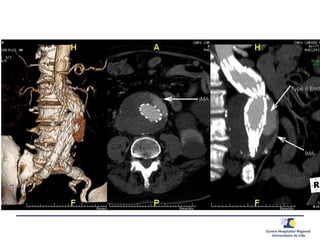

or IMA

ENDOFUITES type 2

TYPE 2 – AMI

• À 1 an:  du diamètre de 1 cm diamètre + EF type 2 and 1b

2ème Procédure

• Angiographie

• Embolisation Type 2

• Embolisation iliaque interne + jambage

d’extension iliaque